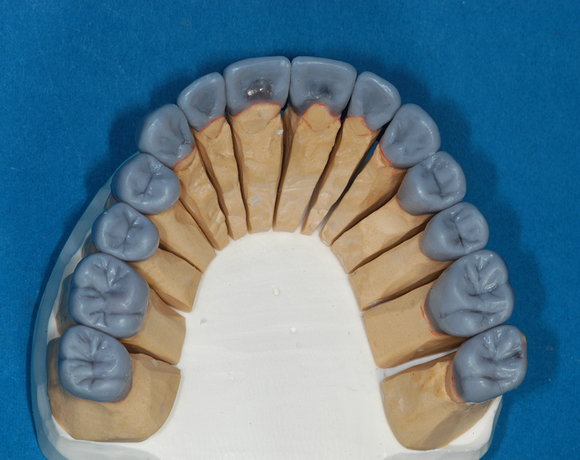

22 Einzelkronen mit Eris for E II

Empress II Presskeramik mit Eris Verblendkeramik bei einer Neuversorgung im Oberkiefer komplett und im Unterkiefer Vollkronen auf den Seitenzähnen.

Ein Projekt aus dem Jahr 2004

Hier wurden der ganze Oberkiefer und die Seitenzähne im Unterkiefer mit neuen Kronen aus Empress 2 und mit Eris Verblendkeramik versorgt.